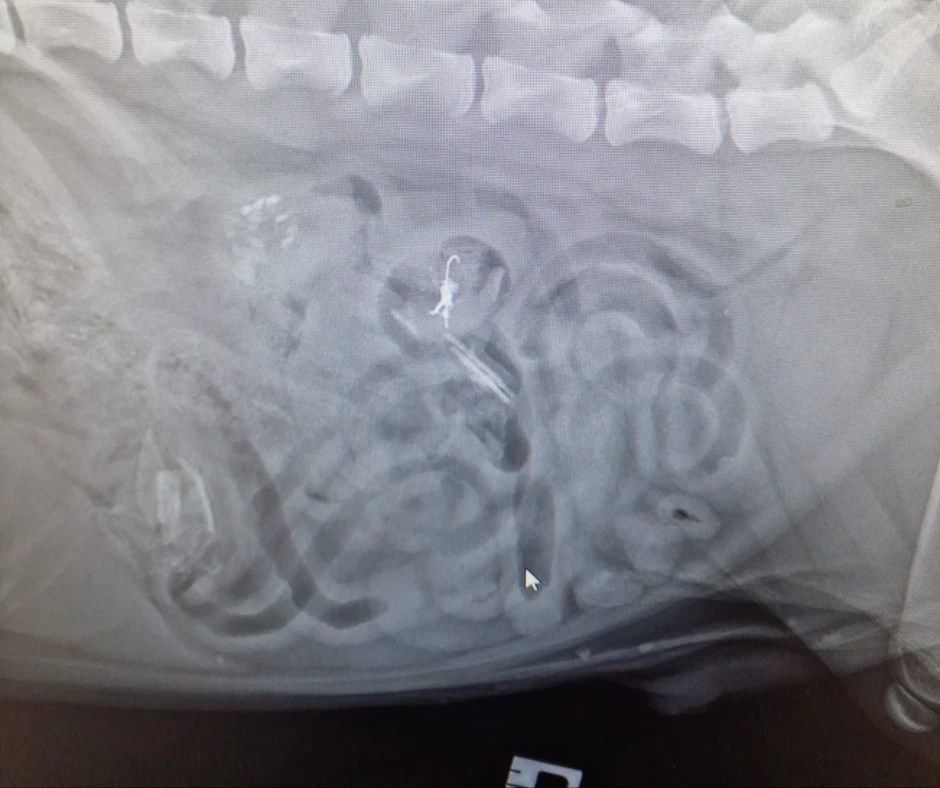

Intestinal obstruction is a serious condition that occurs when the intestines become blocked and cannot pass food, fluid, or gas. Various things, including foreign objects, tumours, and inflammatory conditions, can cause this. Intestinal obstruction can be a life-threatening condition and requires immediate medical attention.

Treatment for intestinal obstruction will depend on the cause of the blockage and may include surgery to remove the obstruction, medications to help relieve symptoms, and supportive care such as fluids and nutrition. It is essential to prevent intestinal obstructions by keeping your dog away from items that may be swallowed, such as small toys or household items, and by ensuring that your dog has a healthy diet.